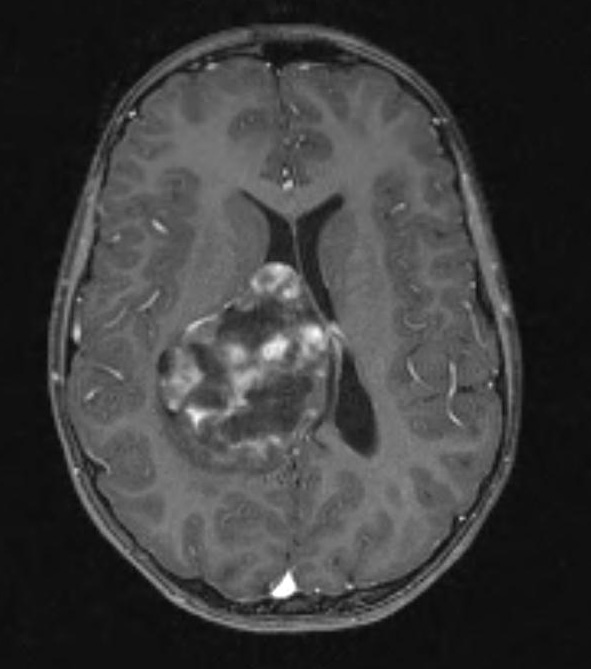

Case 24 ---- 11 year old female, right lateral ventricle (No BRAF FISH test at this time at WUSM) ---- 24A1,2 MRI studies include T1-weighted (24A1) scan and T2-weighted